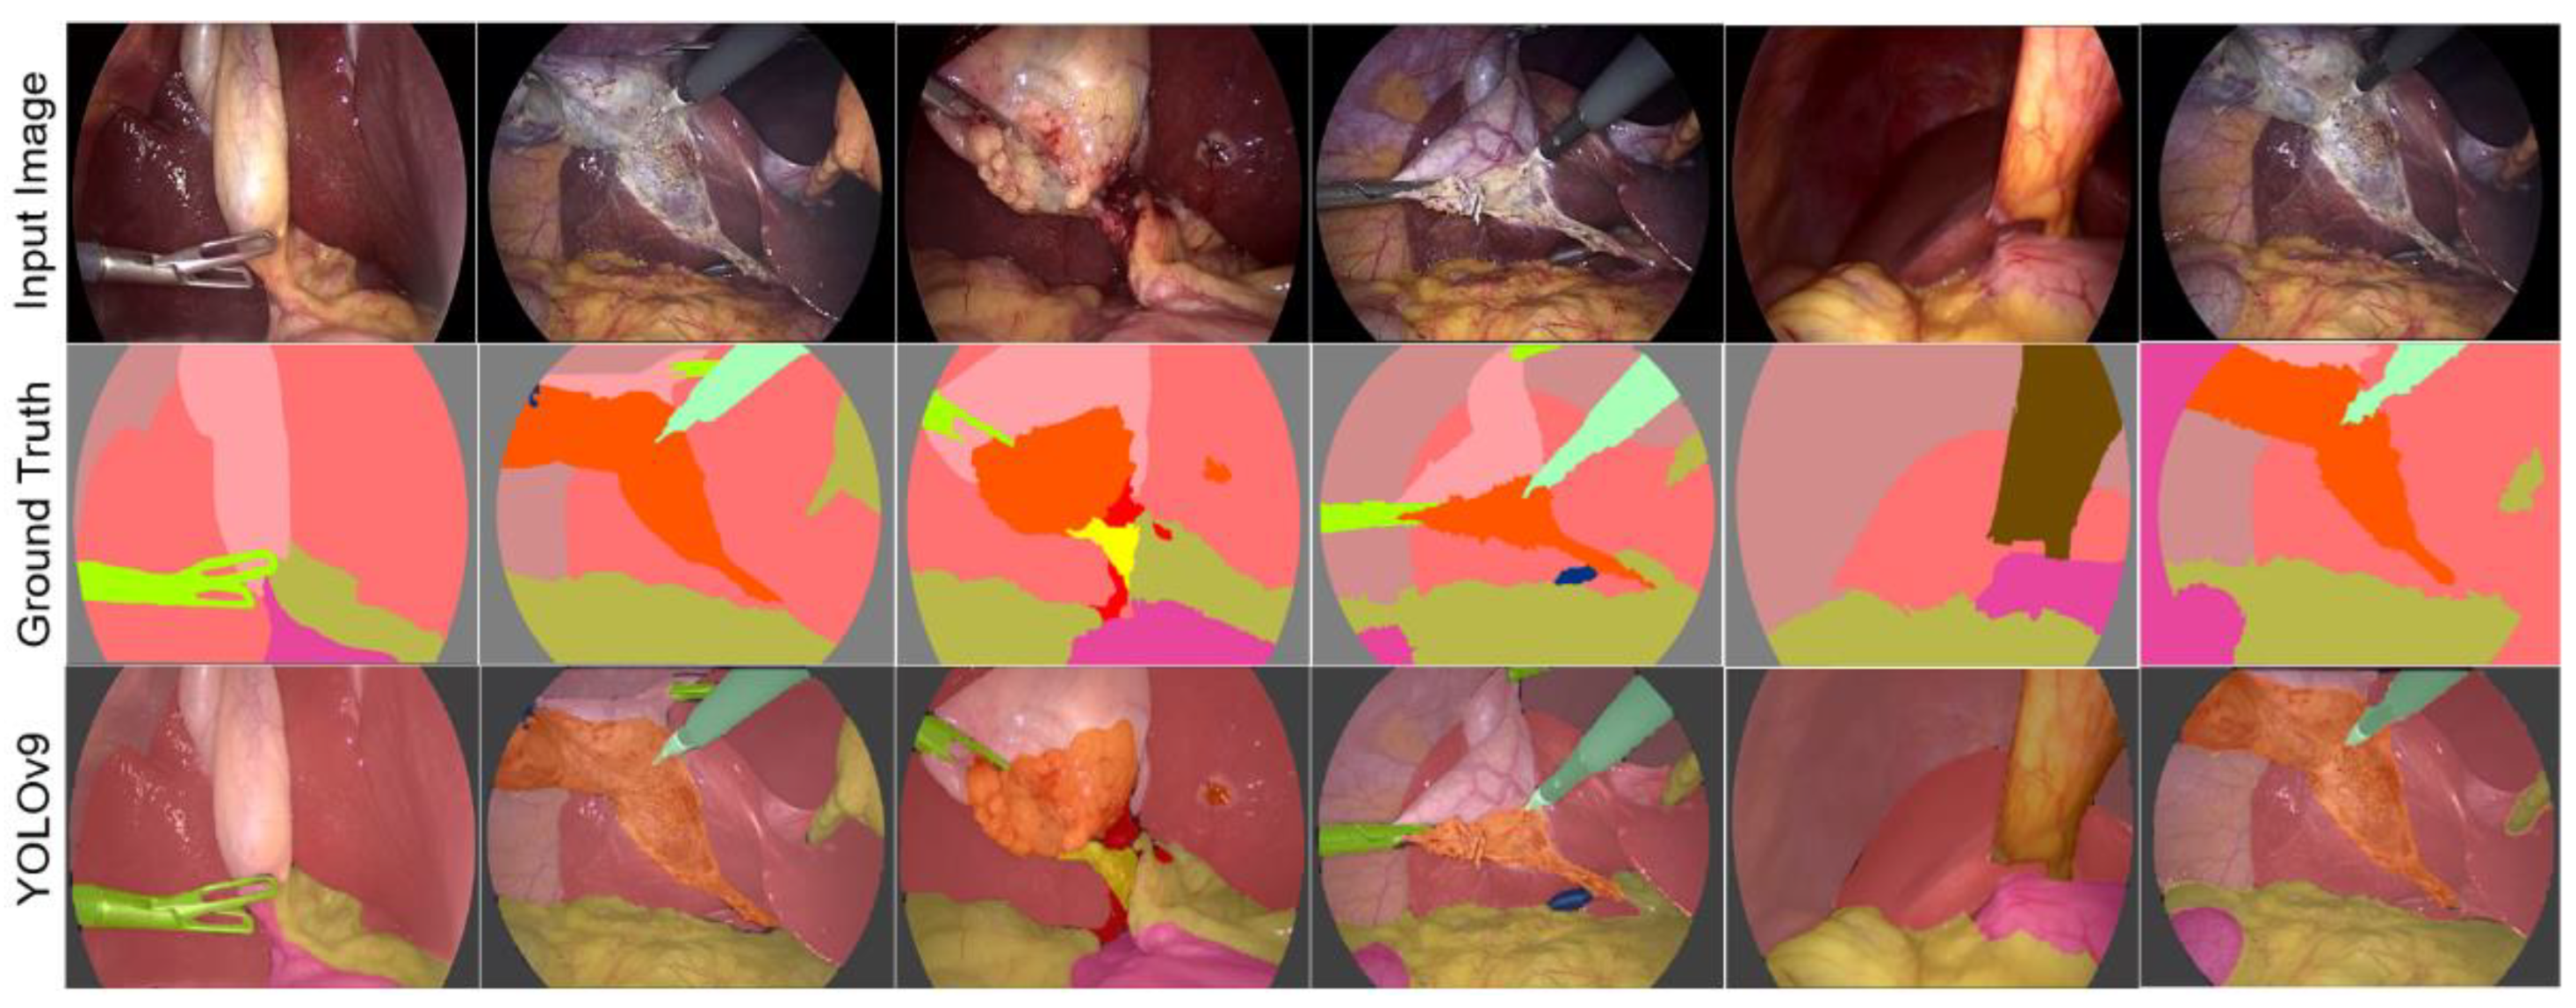

Figure 14 shows the results offered by the YOLOv9 architecture, using the Adam optimizer, the CETL loss function, and the Swish activation function. The number of epochs was set to 30. As can be observed, the results are satisfactory. It is worth noting that, as in all the tests performed, the results are sensitive to improvements by increasing the number of training epochs, among other parameters. It was verified that the proposed parameters allow improving the performance of this DL architecture.

As observed, the results of YOLOv9 present black color regions that do not belong to a specific class. This may be related to the processing carried out to obtain the semantic segmentation, since this architecture is not originally proposed for this purpose, so it is considered that this aspect can be improved.